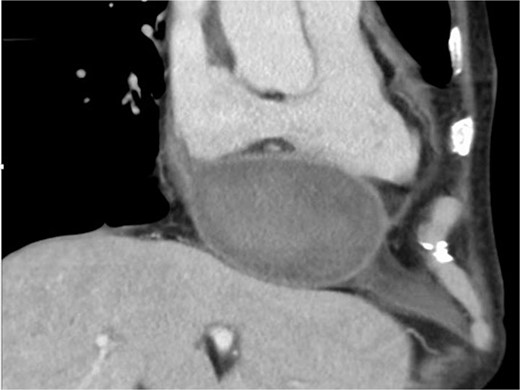

During the first operation, an abscess was discovered in the posterior mitral valve annulus. After removing the vegetation, the mitral valve was replaced (Epic 27 mm; St. Jude Medical, Saint Paul, MN, USA), using the flip-over technique, with the anterior leaflet tissue as reinforcement for the posterior annulus side. Upon cardiopulmonary bypass weaning, bleeding occurred from the posterior surface of the inferior vena cava secondary to LV rupture. Sequentially, the tissue valve was removed, the P2 site of the annulus was covered with a 2 × 4-cm pericardial patch from the inside (Fig. 1), and valve replacement was repeated. The patient recovered without complications and was transferred to another hospital on postoperative Day 39.

The 2 × 4-cm pericardial patch is seen to cover the P2 site of the annulus from the inside during the first operation.